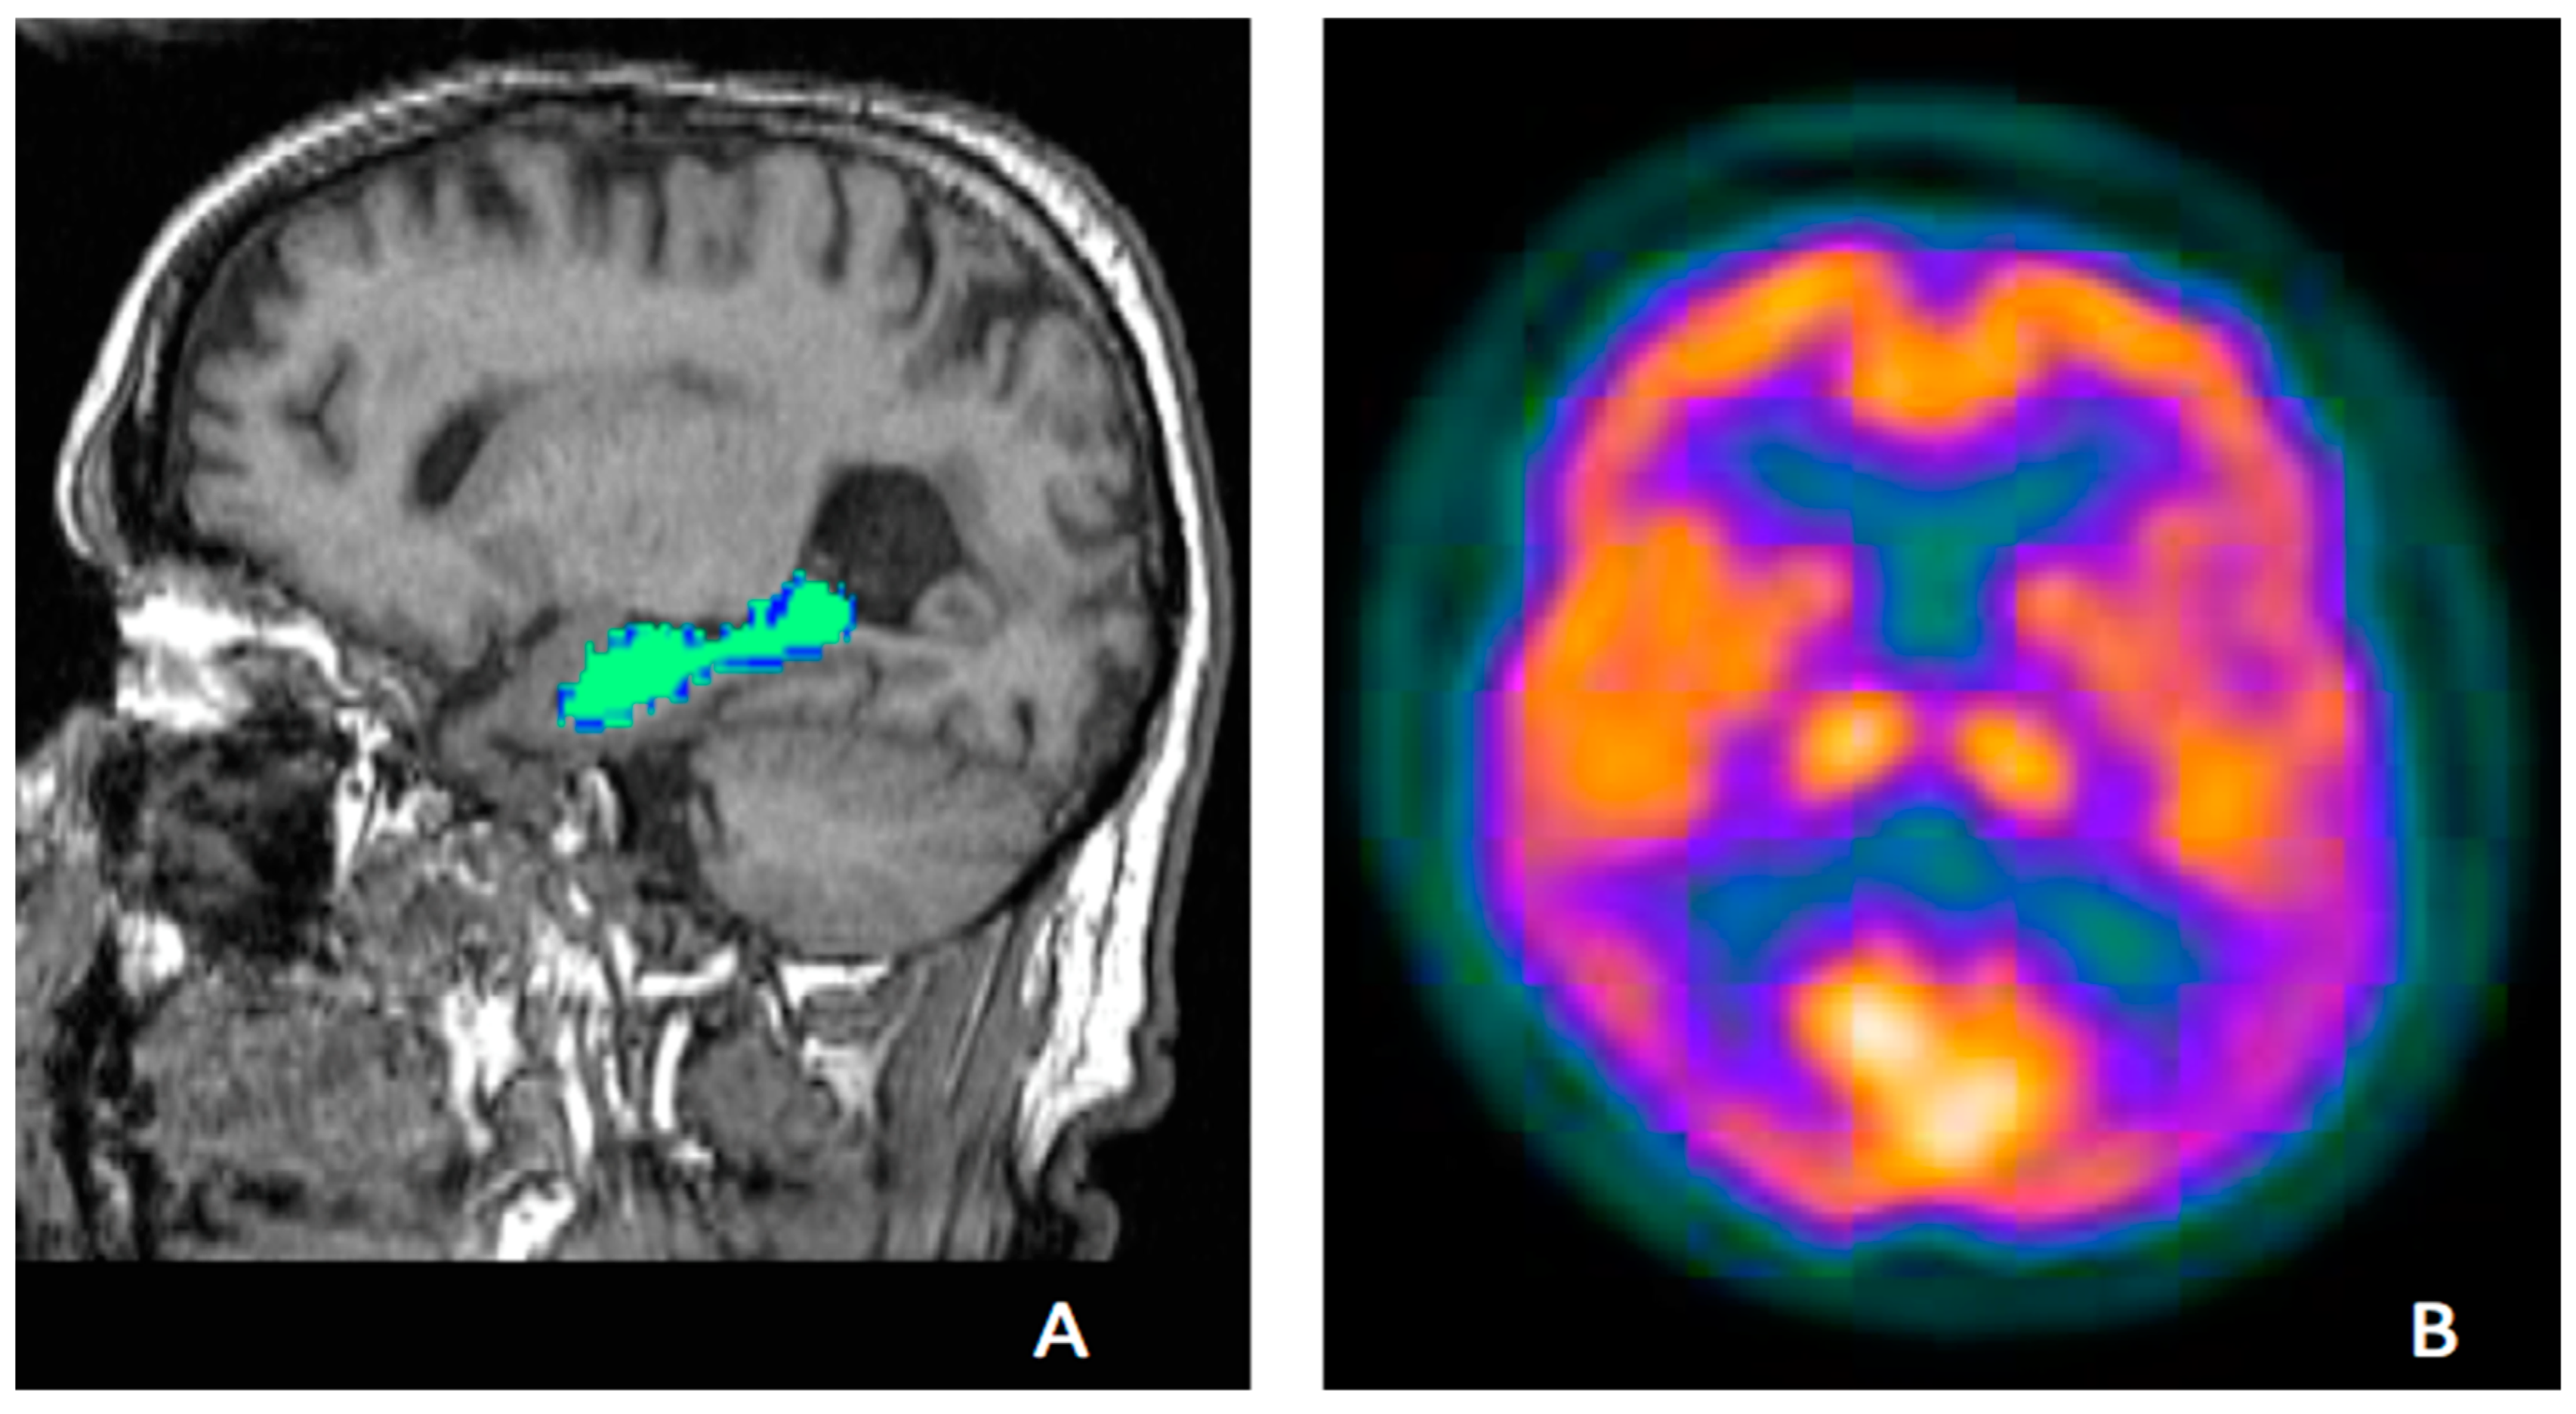

FDG-PET

Amyloid PET

Tau PET